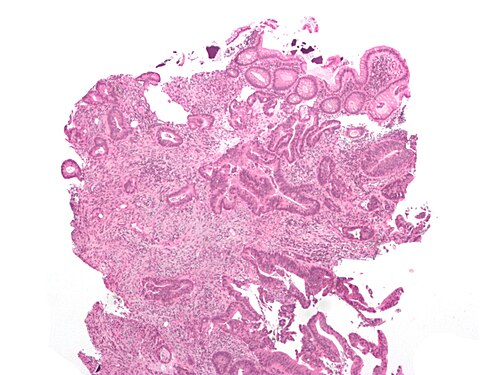

7

Diagnosis?

Inflammatory polyp -- very low mag.jpg

Adenocarcinoma

Colorectal mucosa within normal limits

Ganglioneuroma

Hyperplastic polyp

Inflammatory polyp

Juvenile polyp

Peutz-Jeghers polyp

Sessile serrated adenoma

Traditional serrated adenoma

Tubular adenoma

Tubulovillous adenoma

Villous adenoma

Xanthomatous polyp